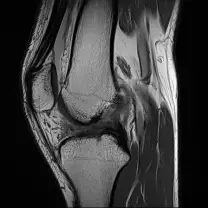

Lazimnya , air radang lutut ini banyak kali terlepas pandang oleh perawat kerana kesukaran untuk mengesannya tanpa menggunakan ultrasound.

Kecederaan ligamen boleh disebabkan renggang, atau koyak pada bahagian ligament dan tendon. Cara untuk mengenalpasti sama ada lutut anda bengkak kerana terseliuh atau ligamen pecah bergantung pada masa dan tahap kesakitan lutut anda.

B. Ligamen terkoyak sepenuhnya: Anterior Cruciate Ligament (ACL) yang menyambungkan bahagian peha dan betis untuk menstabilkan lutut sewaktu pergerakan berpusing. Pemain sukan aktif seperti pemain bola sepak, ragbi dan tenis cenderung untuk mendapat kecederaan ACL ini.